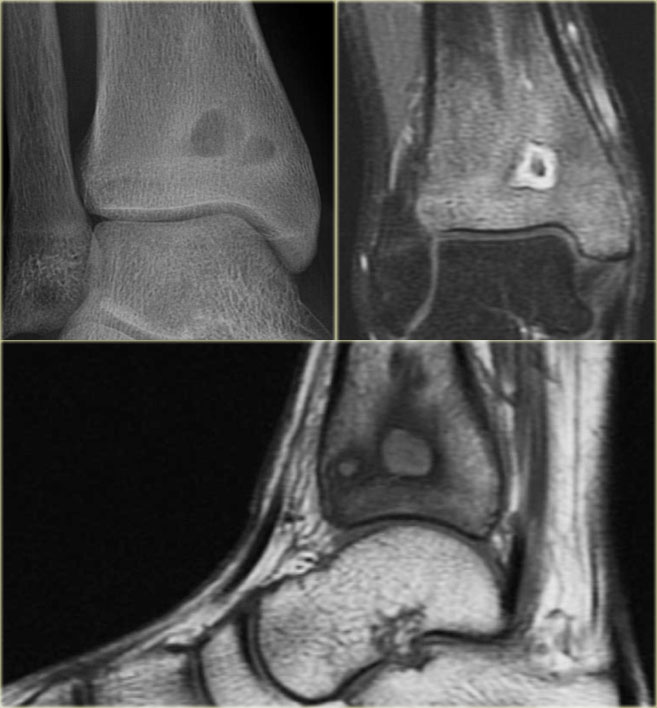

The radiograph shows a well-defined osteolytic lesion in the distal metaphysis of the tibia with surrounding reactive sclerosis.

The coronal T1-weighted Gd-enhanced image with fat-suppression shows a central hypointense focus with thick enhancing zone and peripheral low-intensity rim.

There is extensive bone marrow edema, which enhances.

On the sagittal T1-weighted image notice the low signal intensity rim edging the infectious foci and the low SI of the bone marrow due to edema.

Final diagnosis: Brodies abscess.